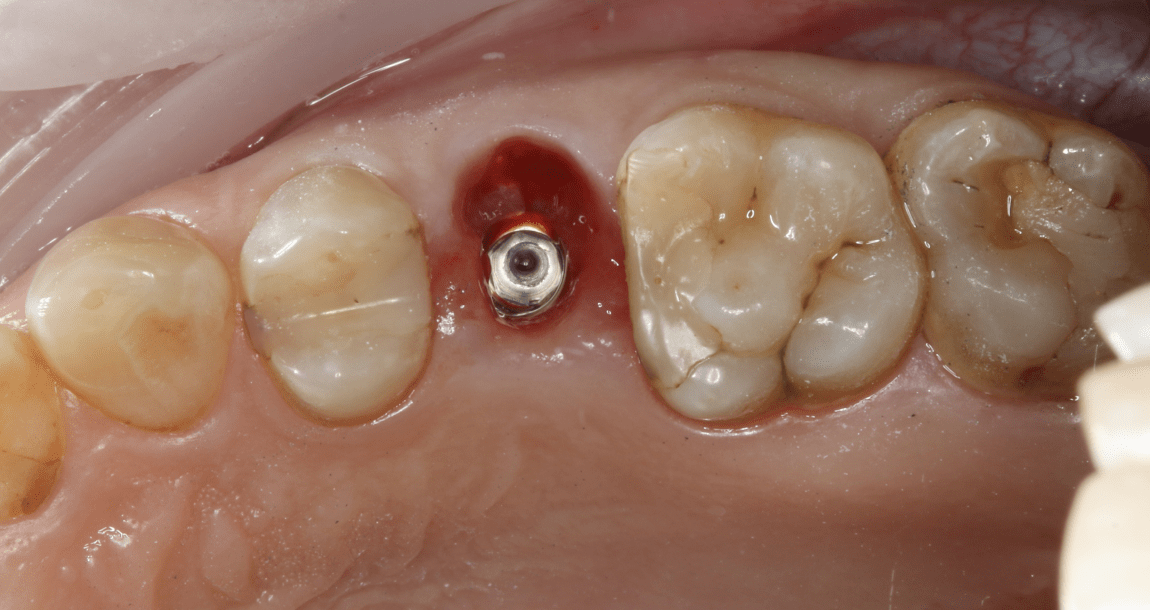

Что происходит с костью после удаления зуба

Костная ткань живёт только там, где получает нагрузку от зуба. Если зуба нет:

При выраженной атрофии уже невозможно поставить имплант без костной пластики — это дополнительная операция, время и деньги.

- кость уменьшается в высоту,

- стенки лунки становятся тоньше,

- объём убывает уже в первый год.